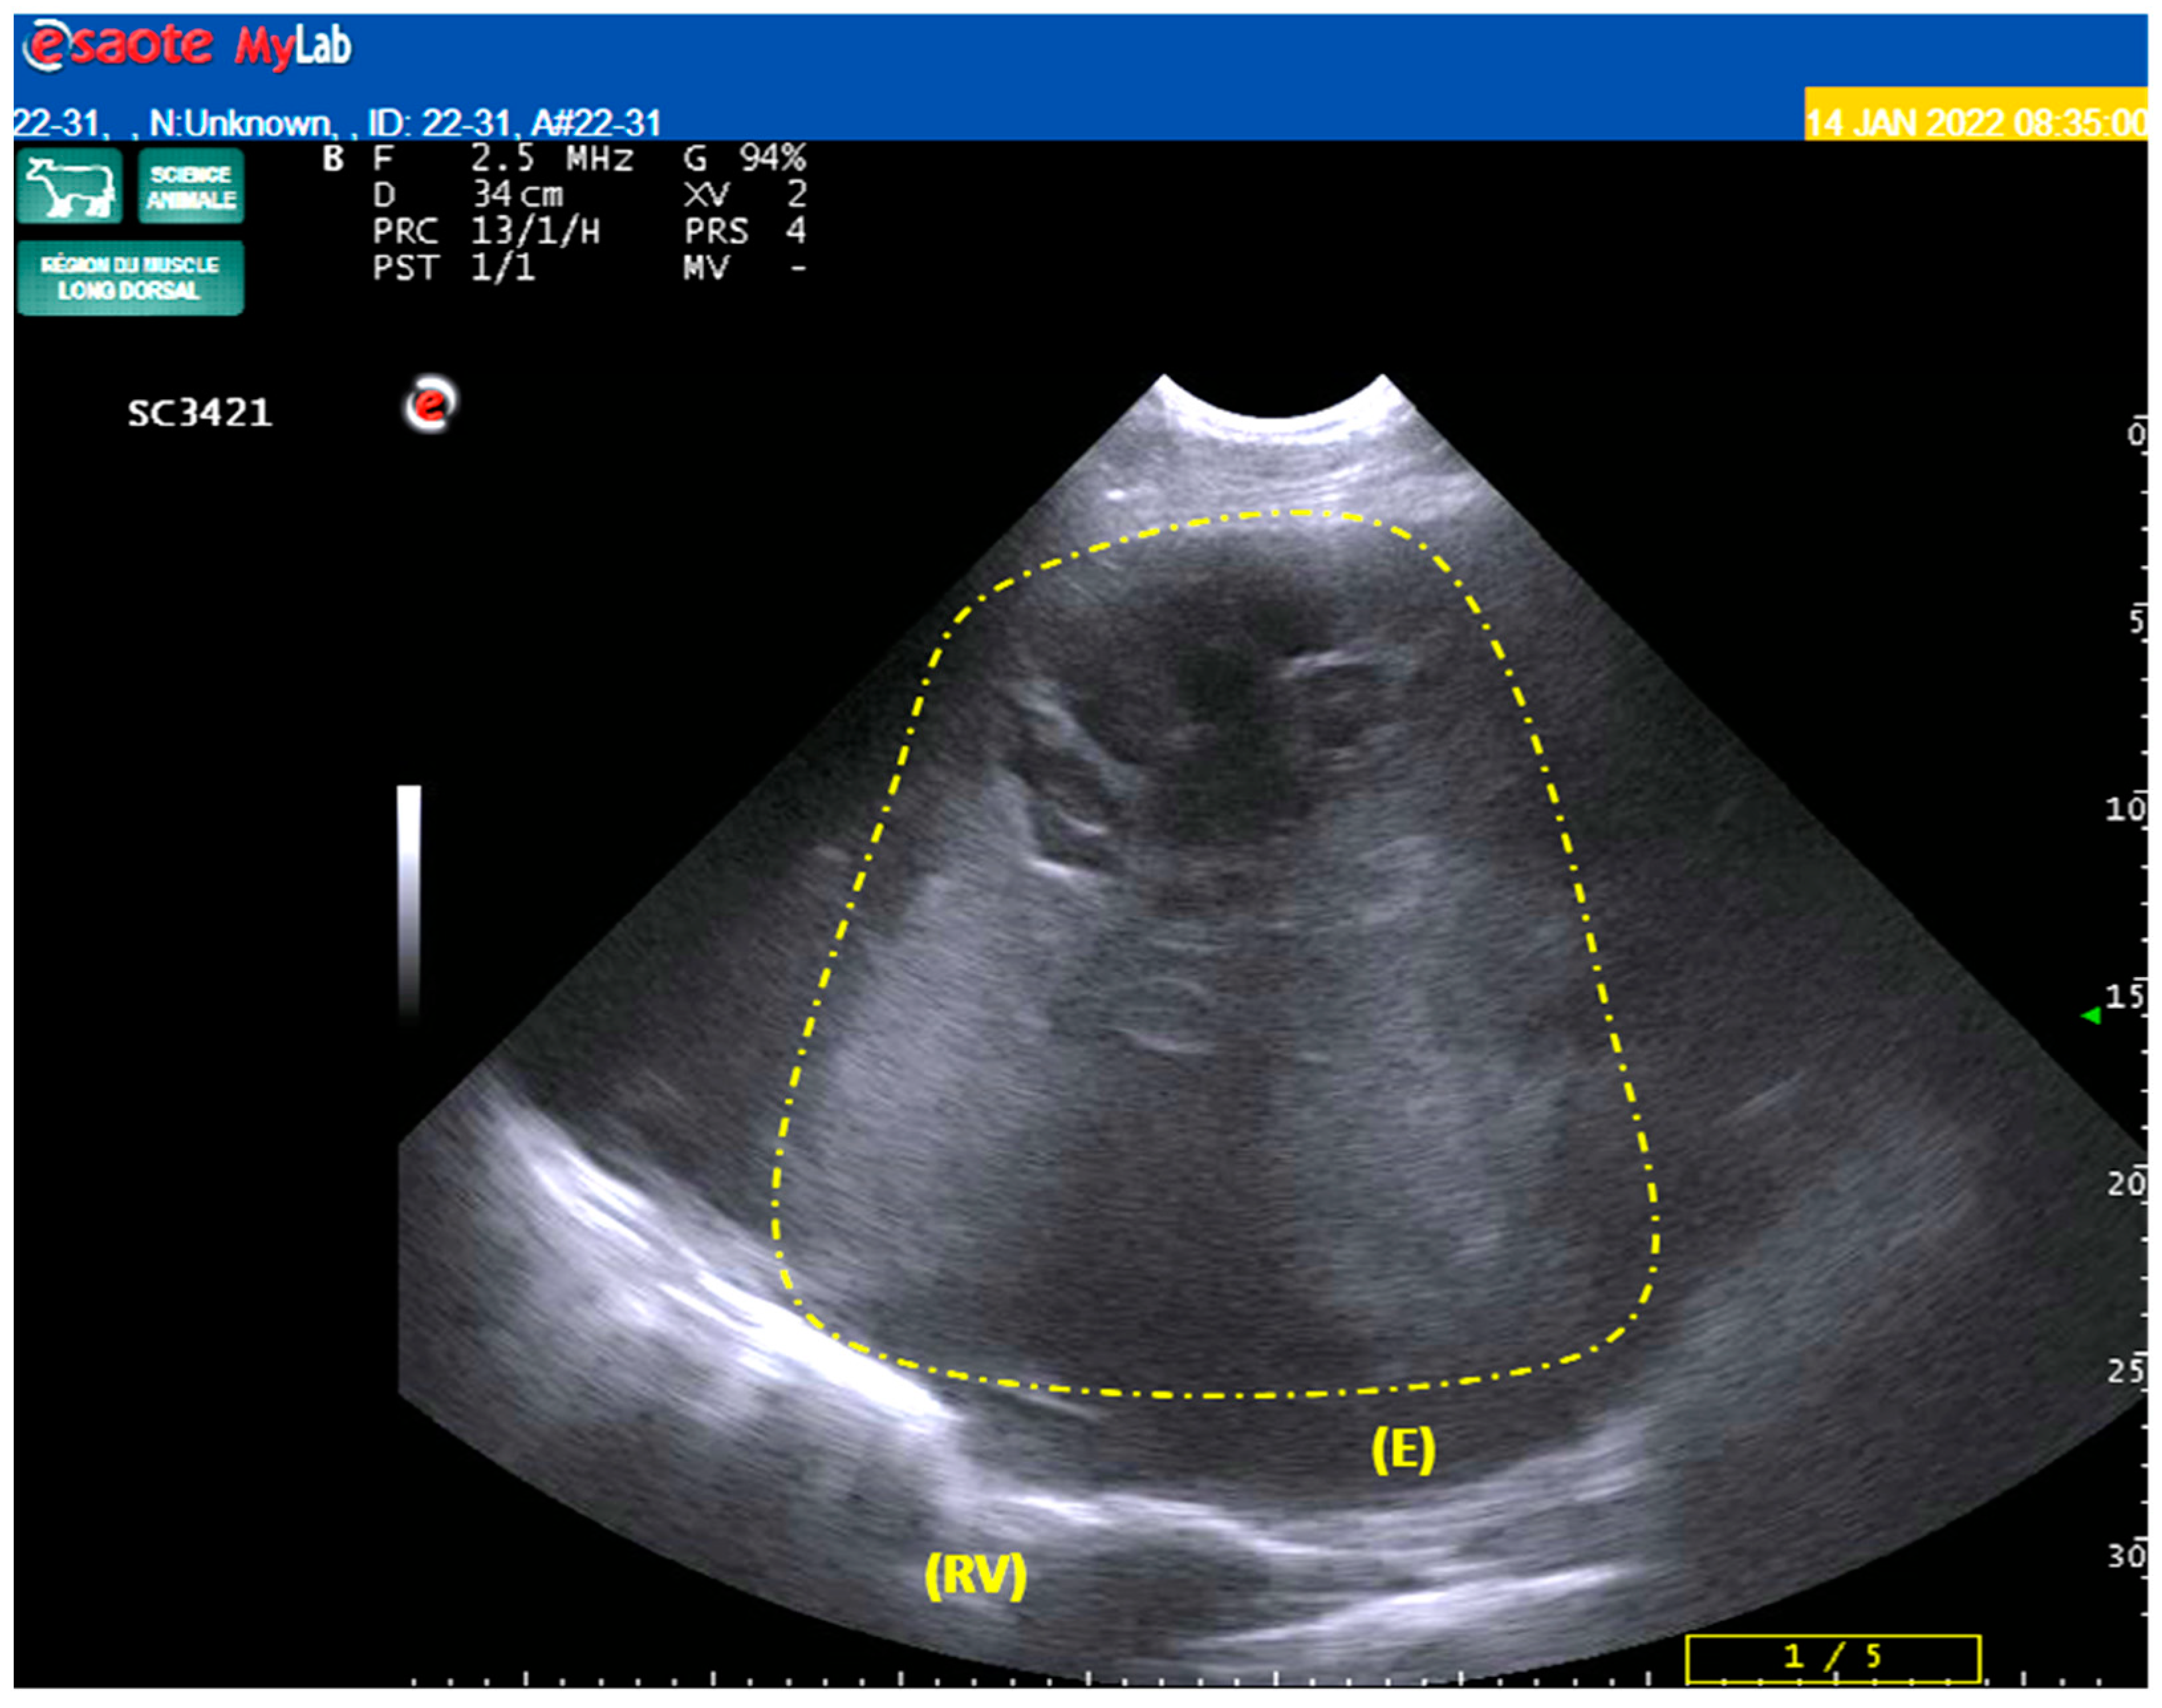

2.1. Case Presentation and Gross Findings